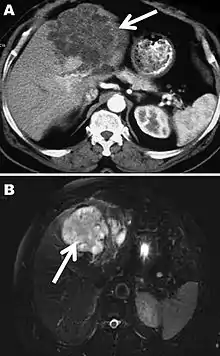

A formal diagnosis of any type of echinococcosis requires a combination of tools that involve imaging techniques, histopathology, or nucleic acid detection and serology. For cystic echinococcosis diagnosis, imaging is the main method—while serology tests (such as indirect hemagglutination, ELISA (enzyme linked immunosorbent assay), immunoblots or latex agglutination) that use antigens specific for E. granulosus verify the imaging results. The imaging technique of choice for cystic echinococcosis is ultrasonography, since it is not only able to visualize the cysts in the body's organs,[30] but it is also inexpensive, non-invasive and gives instant results.[31] In addition to ultrasonography, both MRI and CT scans can and are often used although an MRI is often preferred to CT scans when diagnosing cystic echinococcosis since it gives better visualization of liquid areas within the tissue.[30][32]

As with cystic echinococcosis, ultrasonography is the imaging technique of choice for alveolar echinococcosis and is usually complemented by CT scans since CT scans are able to detect the largest number of lesions and calcifications that are characteristic of alveolar echinococcosis. MRIs are also used in combination with ultrasonography though CT scans are preferred. Like cystic echinococcosis, imaging is the major method used for the diagnosis of alveolar echinococcosis while the same types of serologic tests (except now specific for E. multilocularis antigens) are used to verify the imaging results. It is also important to note that serologic tests are more valuable for the diagnosis of alveolar echinococcosis than for cystic echinococcosis since they tend to be more reliable for alveolar echinococcosis since more antigens specific for E. multilocularis are available.[19] In addition to imaging and serology, identification of E. multilocularis infection via PCR or a histological examination of a tissue biopsy from the person is another way to diagnose alveolar echinococcosis.[30]